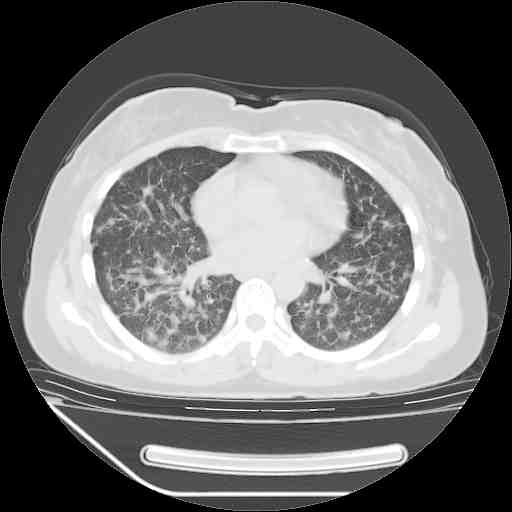

下面是今天刚刚做的,在上海治疗,吃了家属也说不清的一种药,一个月1万左右,

考虑  腺癌肺内转移,治疗较前病灶缩小、减少

肺癌并肺内转移,这种疾病治疗后在影像上看略有好转,不是很显著,但是肿瘤治疗效果影像只是一方面。

支持肺癌并肺内淋巴管炎,  原发灶小了,但转移较前片明显了.

支持右肺下叶周围型肺癌并肺内淋巴管炎,  原发灶小了,但转移较前片明显了.。

标准的细支气管肺泡癌呀!治疗后病情有所控制,也没治愈的迹象!

支持右肺下叶周围型肺癌并肺内淋巴管炎;病灶有所控制。